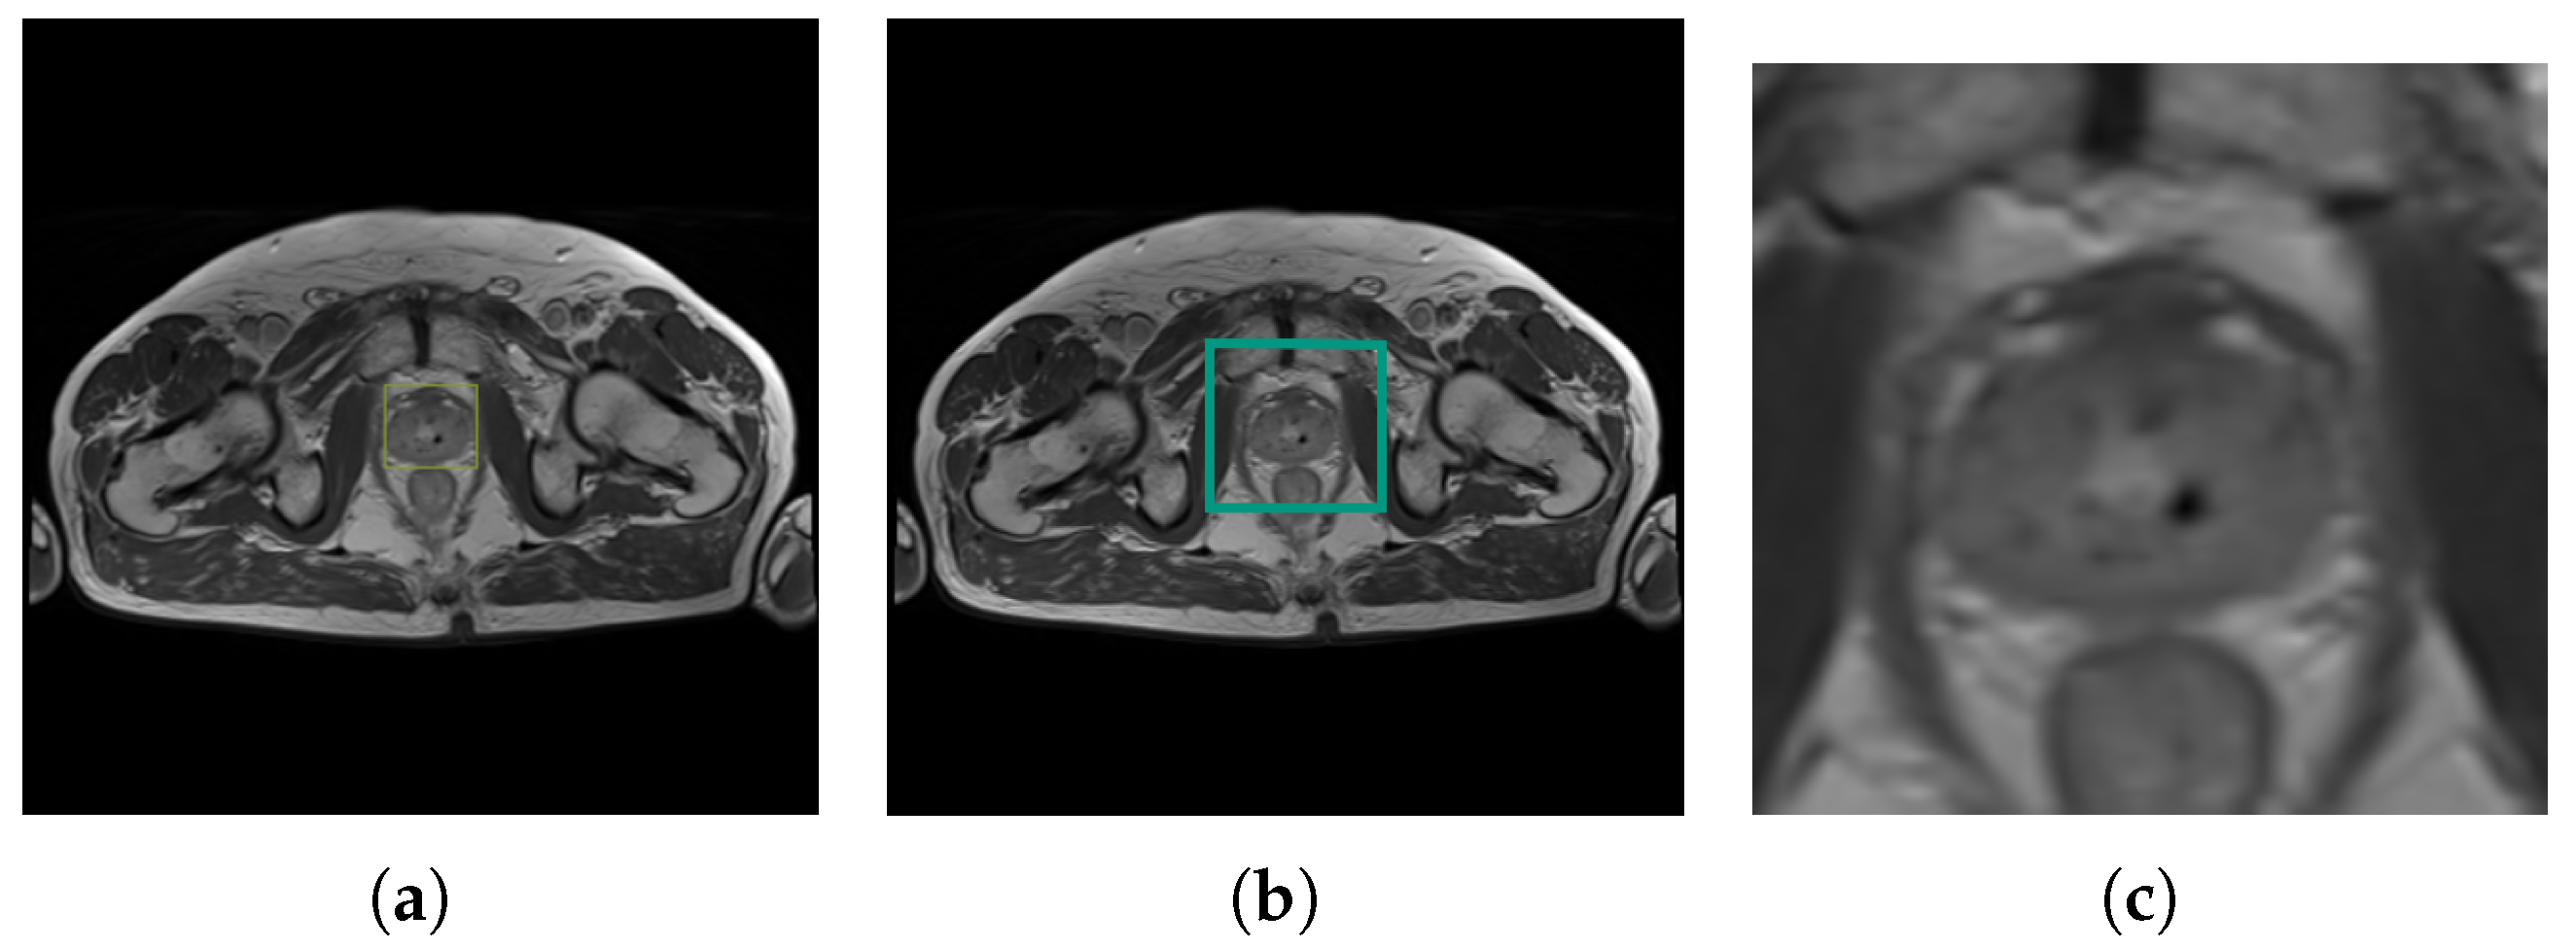

The predicted prostate image was subjected to additional processing, as presented in Figure 7. The object detected by the YOLOv4 with the bounding box label enabled further image processing. Subsequently, an additional 15 px of padding was added. The framed part of the image had been cut out and resized to 256 × 256 pixels. The cropped image was prepared in order to become the input for the U-Net Segmentation Neural Network. The complete post-processing workflow is visualized in Figure 4.

Figure 7.

Post-processing of prostate detection image: (a) detection bounding box, (b) predicted bounding box, and (c) cropped image (U-Net input).